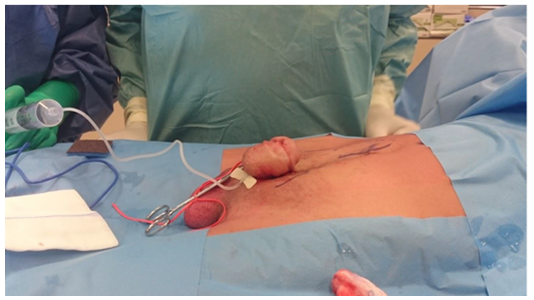

With the aid of the plastic surgeon, an infra-umbilical, abdominal wall Z-plasty was performed. The skin and subcutaneous tissue were mobilized to widen the pre-pubic area and to diminish the dorsal angulation. As such an excellent result was achieved and the erectile angulation was reduced, making intercourse possible. The patient returned home the next day and was very satisfied with the functional and aesthetic result (Figure 1-3).

Figure 2 Abdominal wall Z-plasty.